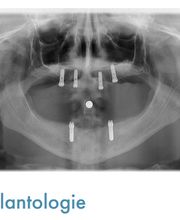

Le Cabinet de Médecine Dentaire du Dr. Christian Molinari, situé idéalement en face de la gare de Moutier, a ouvert ses portes le 1er octobre 2005. Grâce à son emplacement pratique et sa structure moderne, il vous accueille dans un cadre professionnel et chaleureux, où l'ensemble de l'équipe soignante met tout en œuvre pour garantir une expérience sereine et agréable. Le cabinet dispose de places de parking gratuites, réservées exclusivement aux patients, à l'arrière de l'immeuble, ce qui vous permet d’accéder facilement à nos services. À l’intérieur, vous trouverez un environnement entièrement informatisé, avec quatre salles de traitement à la pointe de la technologie, offrant ainsi un large éventail de soins de médecine dentaire moderne. Notre cabinet comprend également un local dédié à la radiologie numérique, incluant une radiographie panoramique, permettant des diagnostics précis et rapides. Grâce à notre équipement de pointe, nous assurons une prise en charge optimale de chaque patient. Les soins que nous proposons incluent : - Dentisterie esthétique : Nous offrons des solutions pour améliorer l'apparence de vos dents, telles que les facettes, les blanchiments, et les restaurations esthétiques. - Prophylaxie : Pour maintenir une santé bucco-dentaire optimale, nous mettons en place des programmes de prévention et de nettoyage des dents. - Parodontologie : Nous traitons les problèmes liés aux gencives et à l'os, avec des soins adaptés pour prévenir et traiter les maladies parodontales. - Implantologie : Nous pratiquons la pose d'implants dentaires, offrant ainsi une solution durable et fiable pour le remplacement de dents manquantes. - Prothèses dentaires fixes et amovibles : Nous proposons des prothèses adaptées à vos besoins, qu'elles soient fixes ou amovibles, pour restaurer la fonction et l'esthétique de votre dentition. - Traitement au laser des tissus mous : Nous utilisons des lasers de dernière génération pour traiter les problèmes liés aux gencives, aux aphtes, à l'herpès, et autres affections des tissus mous. Le cabinet est également équipé de deux types de laser afin de proposer des traitements à la pointe de la technologie, garantissant des soins plus précis, moins invasifs et plus confortables pour nos patients. Notre équipe dynamique de professionnels se tient à votre disposition pour vous offrir un service personnalisé, avec un souci constant de qualité et de bien-être. Vous serez accueilli dans une grande réception et une salle d'attente moderne, dans une ambiance calme et détendue. Au Cabinet de Médecine Dentaire du Dr. Christian Molinari, nous mettons un point d’honneur à vous offrir les meilleurs soins dentaires dans un environnement sûr, confortable et respectueux de vos besoins. N’hésitez pas à prendre rendez-vous pour découvrir notre approche unique de la santé dentaire.